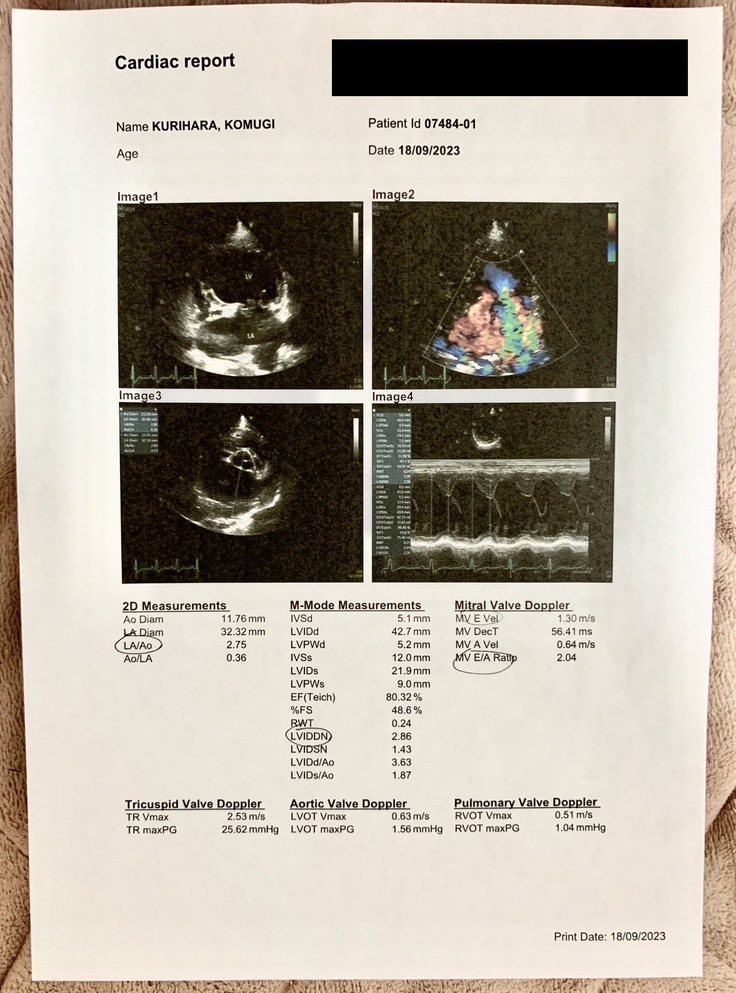

▽エコー写真

※循環器専門病院からの掲載許可をいただいています

▽検査結果の説明(一部)